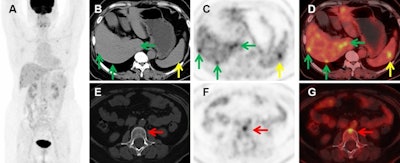

Images of a 56-year-old female with recurrence of choriodal melanoma two years after left eye enucleation. (A) Maximum intensity projection (MIP) images showed multiple metastatic lesions. B-D Axial CT (B), PET (C), and fused PET/CT (D) images showed liver metastasis (green arrows) and splenic metastasis (yellow arrows). E-G images showed an L2 vertebral metastasis without density changes (red arrows). Cancer Imaging